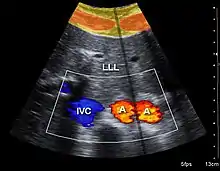

Both abdominal and endoanal ultrasound are frequently used in gastroenterology and colorectal surgery. In abdominal sonography, the major organs of the abdomen such as the pancreas, aorta, inferior vena cava, liver, gall bladder, bile ducts, kidneys, and spleen may be imaged. However, sound waves may be blocked by gas in the bowel and attenuated to differing degrees by fat, sometimes limiting diagnostic capabilities. The appendix can sometimes be seen when inflamed (e.g.: appendicitis) and ultrasound is the initial imaging choice, avoiding radiation if possible, although it frequently needs to be followed by other imaging methods such as CT. Endoanal ultrasound is used particularly in the investigation of anorectal symptoms such as fecal incontinence or obstructed defecation. It images the immediate perianal anatomy and is able to detect occult defects such as tearing of the anal sphincter. Ultrasonography of liver tumors allows for both detection and characterization.[13]